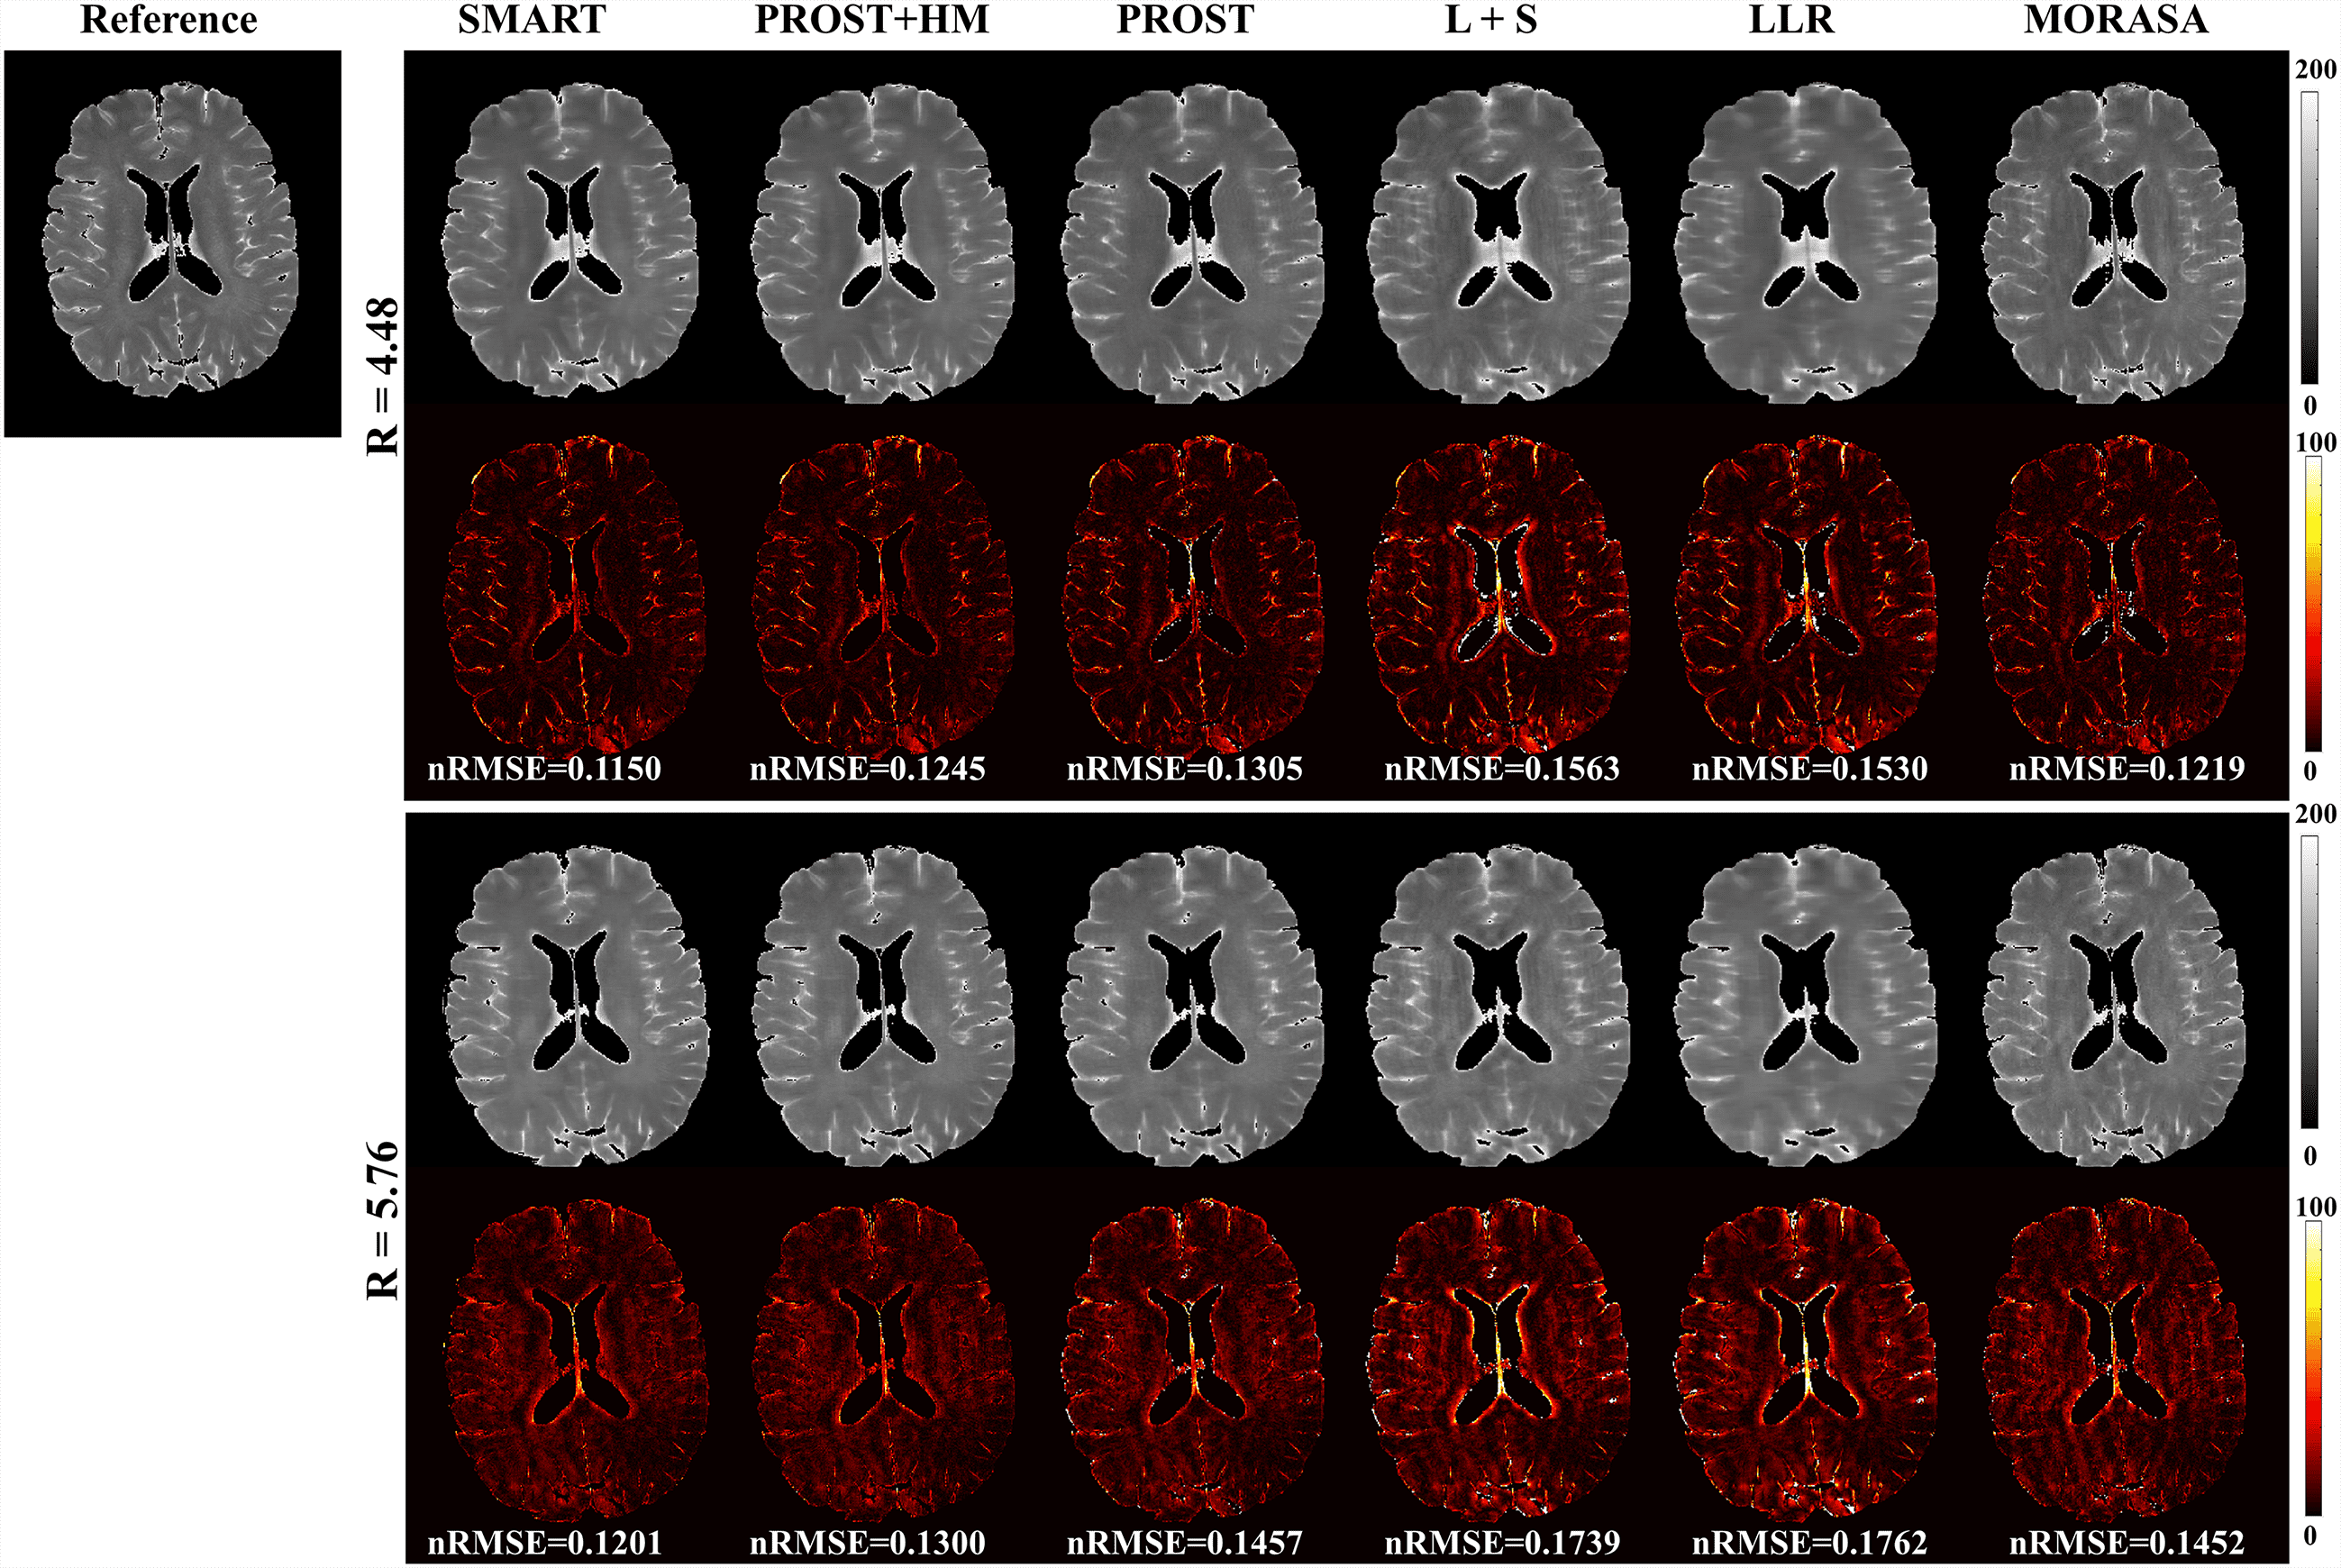

4.3 Prospective 2D Reconstruction

Fig. 6 shows the prospective reconstructed -weighted images (at TSL = 40 ms) from another volunteer and the magnified images using the SMART, PROST + HM, PROST, L + S, LLR, and MORASA methods. Visual artifacts can be observed in the magnified images of reconstructions at all accelerating factors using the L + S and LLR methods. The images reconstructed using the PROST + HM and PROST methods were blurred compared to those reconstructed using the SMART method. Some image details (namely, the blood vessel marked in a yellow arrow) can narrowly be seen in the reconstructions using the PROST + HM and MORASA methods and disappeared in the reconstruction using the PROST method at R = 5.76. In contrast, the image details were well preserved using the SMART method. The maps reconstructed using the methods above are shown in supplementary information Fig. S4. Similar conclusions can be drawn from the maps.